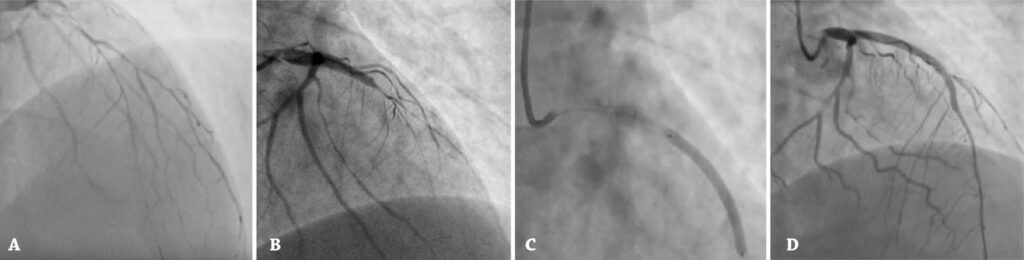

Um homem de 28 anos com história pregressa de abuso de drogas foi encaminhado para coronariografia de emergência após parada cardíaca. O eletrocardiograma pós-ressuscitação mostrou elevação do segmento ST em V1-V4. A angiografia mostrou dissecção espontânea da artéria coronária, multiarterial e em diversos segmentos. Devido à instabilidade clínica, o paciente foi submetido à intervenção coronária percutânea da artéria descendente anterior. A prevalência da dissecção espontânea da artéria coronária como causa de síndrome coronariana aguda em homens é infrequente. No entanto, nos casos suspeitos, ela deve ser excluída. A parada cardiorrespiratória é um quadro incomum na dissecção espontânea da artéria coronária, e a intervenção coronária percutânea como modalidade terapêutica ainda é uma questão em debate.